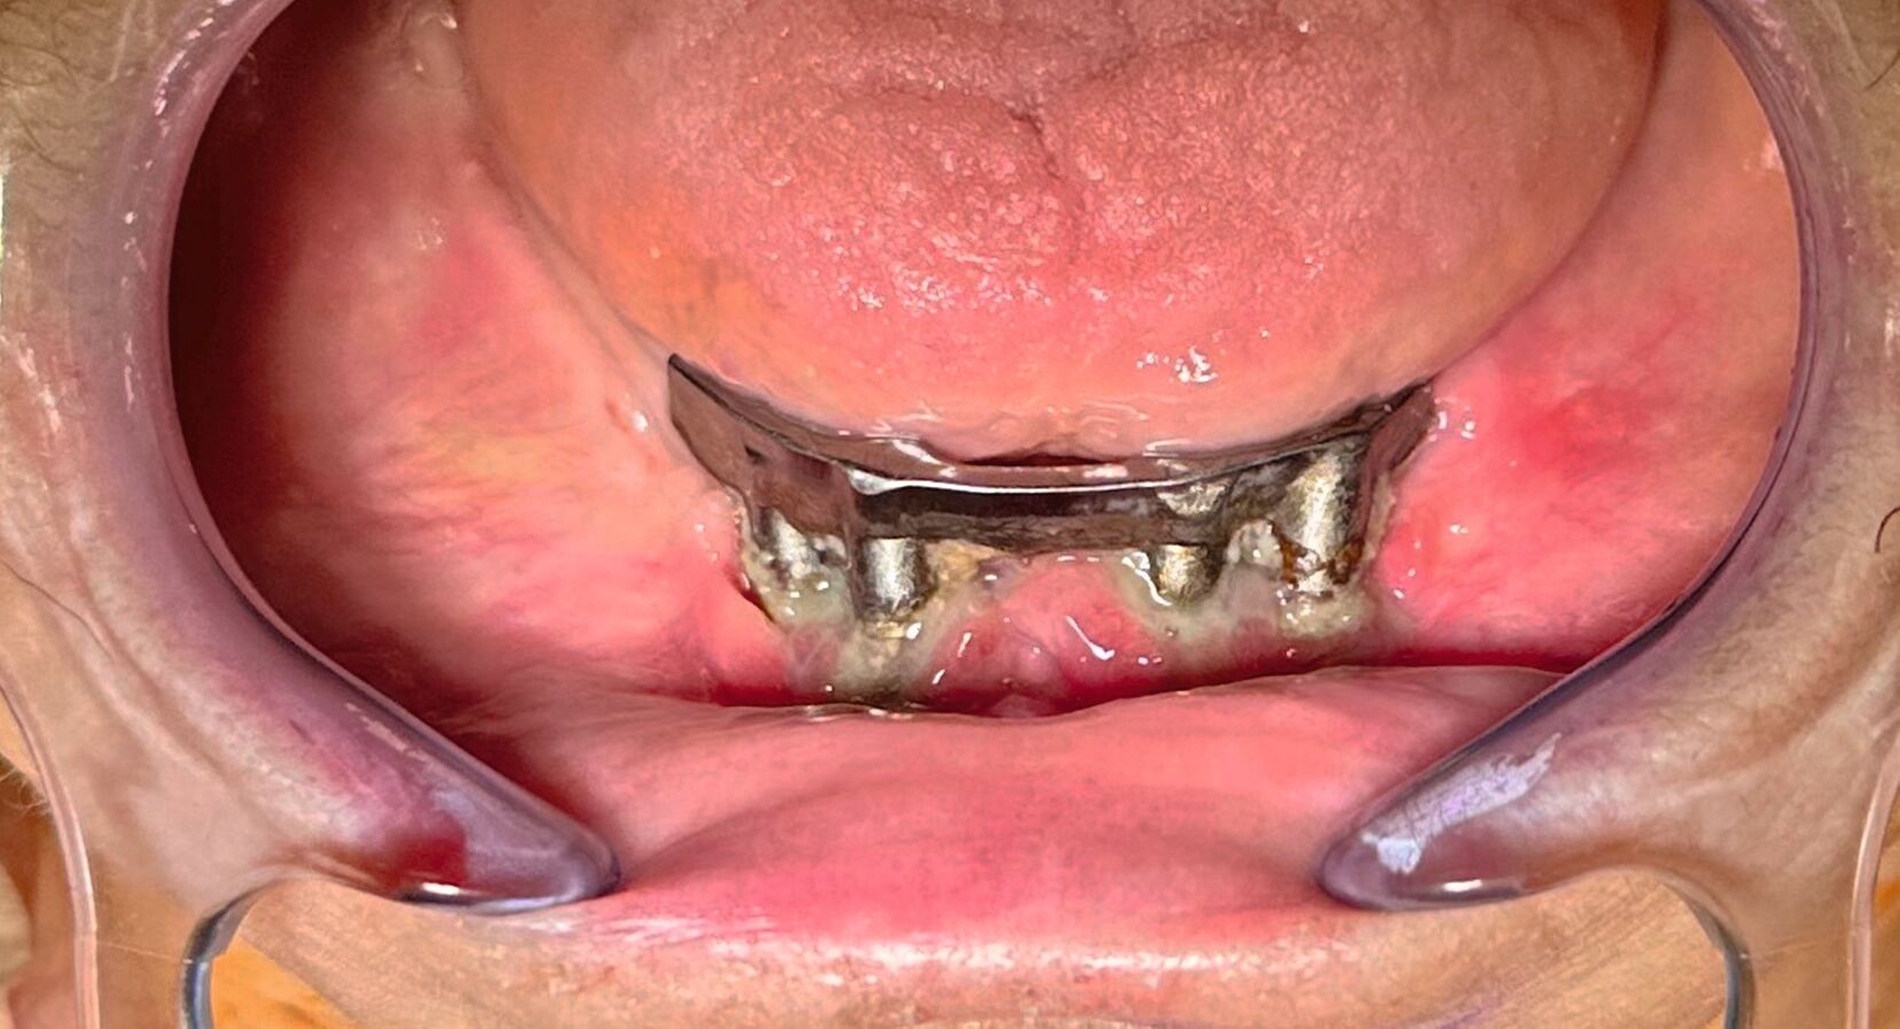

In der klinischen Untersuchung zeigte sich extraoral am linken Unterkieferkorpus eine dezente, jedoch stark druckdolente Schwellung. Aufgrund der abnormen Beweglichkeit des Unterkiefers in diesem Bereich konnte bereits klinisch eine Unterkieferfraktur diagnostiziert werden. Die Patientin war unbezahnt und im Oberkiefer mit einer auf den Implantaten 16, 15, 14, 24, 25, 26 und im Unterkiefer mit einer auf den Implantaten 33, 32, 42, 43 getragenen Prothese versorgt. Die Implantate wurden vor ungefähr 15 Jahren inseriert, wobei die Patientin nach eigenen Angaben seit mindestens zehn Jahren keinen zahnärztlichen Kontrolltermin mehr wahrgenommen hatte. Die Mundhygiene zeigte sich in einem desolaten Zustand, die Implantate wiesen ausgeprägte weiche und harte Beläge mit periimplantärem Blut- und Pusaustritt auf Sondierung auf, wobei die oberen Implantatgewinde bereits exponiert waren. Die periimplantäre Gingiva war massiv gerötet und geschwollen. An allen Implantaten waren Sondierungstiefen von über 10 mm messbar. Die Stegkonstruktion im Unterkiefer war klinisch fest, die Implantate im Oberkiefer bereits erst- beziehungsweise zweitgradig gelockert. Distal des Implantats in regio 26 war die Sondierung der Kieferhöhle mit einer MAV-Sonde möglich.